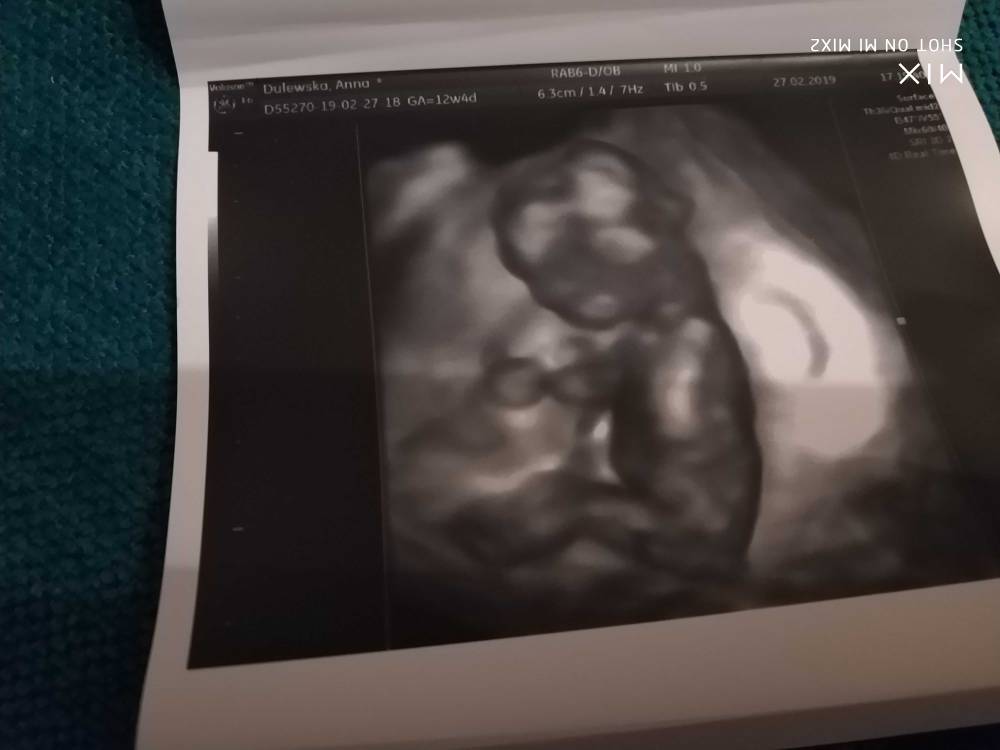

Hej dziewczynki melduje że wszystko ok [emoji6] dzidzia piękna, prawie 6cm, piękny nosek. Chyba spała, z początku się wystraszyłam że coś się dzieje ale lekarz puścił serduszko i pięknie bije. Przepływy dobre, Nt wyszło lekko podwyższone bo 2,36mm ale razem z innymi wynikami wychodzi dobrze. Ryzyko wg USG też wyszło ok. Za dwa tyg będą wyniki z krwii. Doktor powiedział że z USG maluch zdrowy. No i na 70% będzie dziewczynka [emoji7][emoji7] ale póki co się nie nastawiać [emoji6] zdjęć dostaliśmy tyle z tego jednego USG że przez całą ciążę z synem tyle nie miałam [emoji23]

Zobacz załącznik 947066Zobacz załącznik 947067